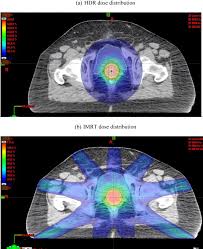

A Dosimetric Analysis Of Intensity Modulated Radiation Therapy Imrt As An Alternative To Adjuvant High Dose Rate Hdr Brachytherapy In Early Endometrial Cancer Patients International Journal Of Radiation Oncology Biology Physics